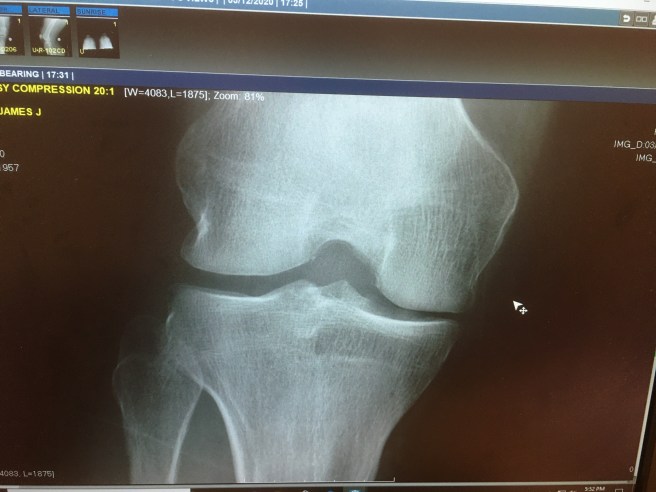

That is my knee in a pic I took, but I had taken the pic before she gave me her less-than-enthusiastic approval to secretly take a pic. Do they have cameras in the exam rooms? Hmmm. Mental note to keep my pants on next time, which is what the doctor suggested, too.